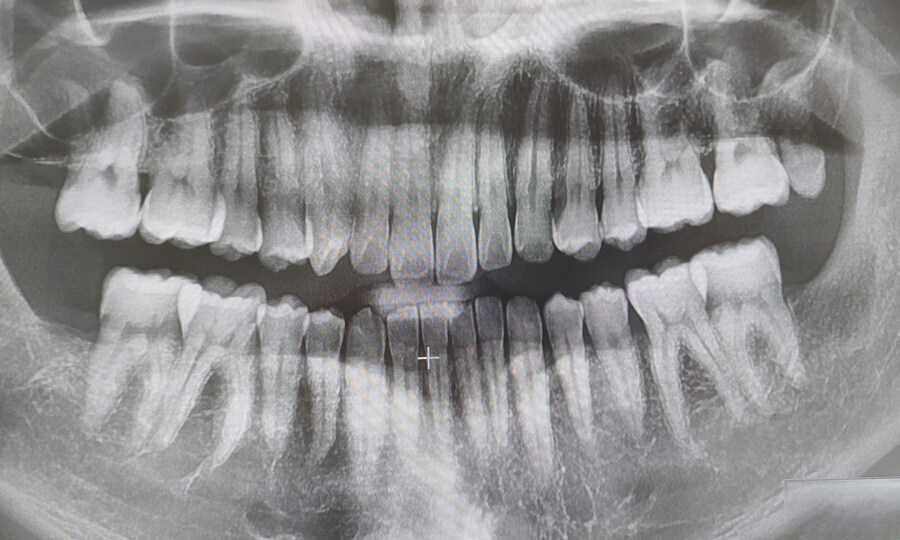

X레이 사진 상 오른쪽 위. 송곳니처럼 작게 자라난 사랑니. 원래 나는 이 사랑니만큼은 몸 안에 남겨두고 싶었어. 여타 사랑니와 달리 별 말썽을 부리지 않았고, 더해 ‘사랑니’라는 이름에서 오는 기운이 있었으니까. 이 사랑니마저 뽑으면 평생 사랑 못할 것 만 같은 미신이랄까...

여하튼. 사랑니 4개를 다 뽑았겠다, 더 이상 치과에 오고 싶지 않지만, 아직 난관이 남았어. X레이 사진 기준 왼쪽 아래 어금니에 충치. 하필이면 인접면 충치.